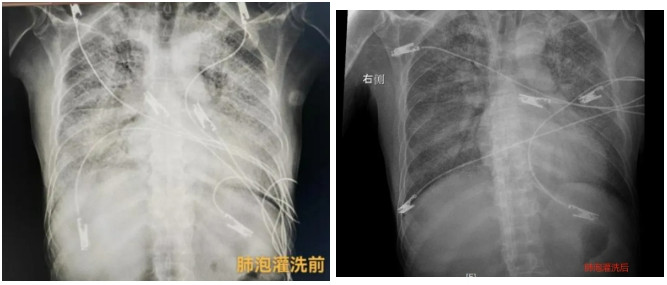

▲肺泡灌洗前(左)和肺泡灌洗后(右)

术后1小时,影像学复查显示,高先生的肺部情况明显改善。经过充分评估,先后撤除ECMO、拔除气管插管。他的神志清楚,对在场的医护人员竖起大大的拇指。